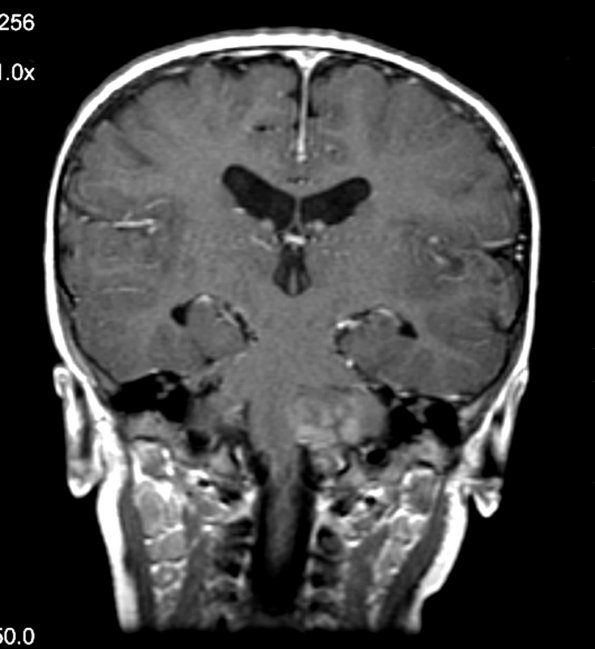

MRI studies of T1-weighted contrast applied scans have a prominent nodular appearance.